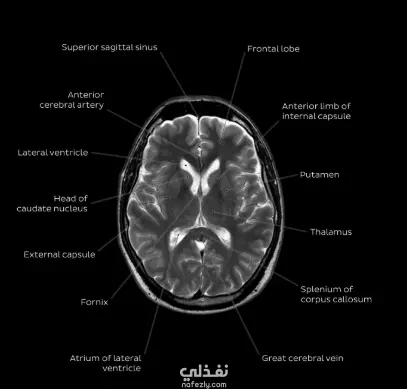

وصف المشروع: مشروع تقني متقدم يهدف إلى مساعدة الأطباء في الكشف المبكر عن أورام الدماغ من خلال تحليل صور الرنين المغناطيسي (MRI). قمت ببناء وتدريب نموذج ذكاء اصطناعي (Deep Learning Model) قادر على التمييز بين الصور السليمة والصور المصابة بدقة عالية جداً، مما يقلل من نسبة الخطأ البشري ويوفر الوقت في التشخيص. المواصفات التقنية (Tech Stack): اللغة المستخدمة: Python. المكتبات الأساسية: TensorFlow / Keras (أو PyTorch حسب ما استخدمت)، OpenCV لمعالجة الصور، NumPy، و Pandas. الخوارزمية: Convolutional Neural Networks (CNN). التقنيات المستخدمة: Data Preprocessing: معالجة الصور (Resizing, Normalization, Noise Reduction). Data Augmentation: لزيادة دقة النموذج وتجنب الـ Overfitting. Evaluation Metrics: قياس الأداء باستخدام (Accuracy, Precision, Recall, F1-Score). النتائج المحققة (Achievements): وصلت دقة النموذج (Accuracy) إلى [اكتب النسبة اللي وصلتلها، مثلاً 97%] على مجموعة بيانات الاختبار. استخراج تقارير بصرية توضح الـ Loss & Accuracy Curves ومصفوفة الارتباك (Confusion Matrix). تسليم الكود البرمجي بملف Jupyter Notebook منظم ومشروح بالكامل لسهولة المراجعة. ما قدمته في هذا المشروع: تجميع وتجهيز قاعدة بيانات صور الرنين المغناطيسي. تصميم معمارية الشبكة العصبية (Model Architecture). عملية التدريب (Training) والتحسين (Fine-tuning) للبارامترات. اختبار النموذج على بيانات جديدة لم يراها من قبل لضمان كفاءته.